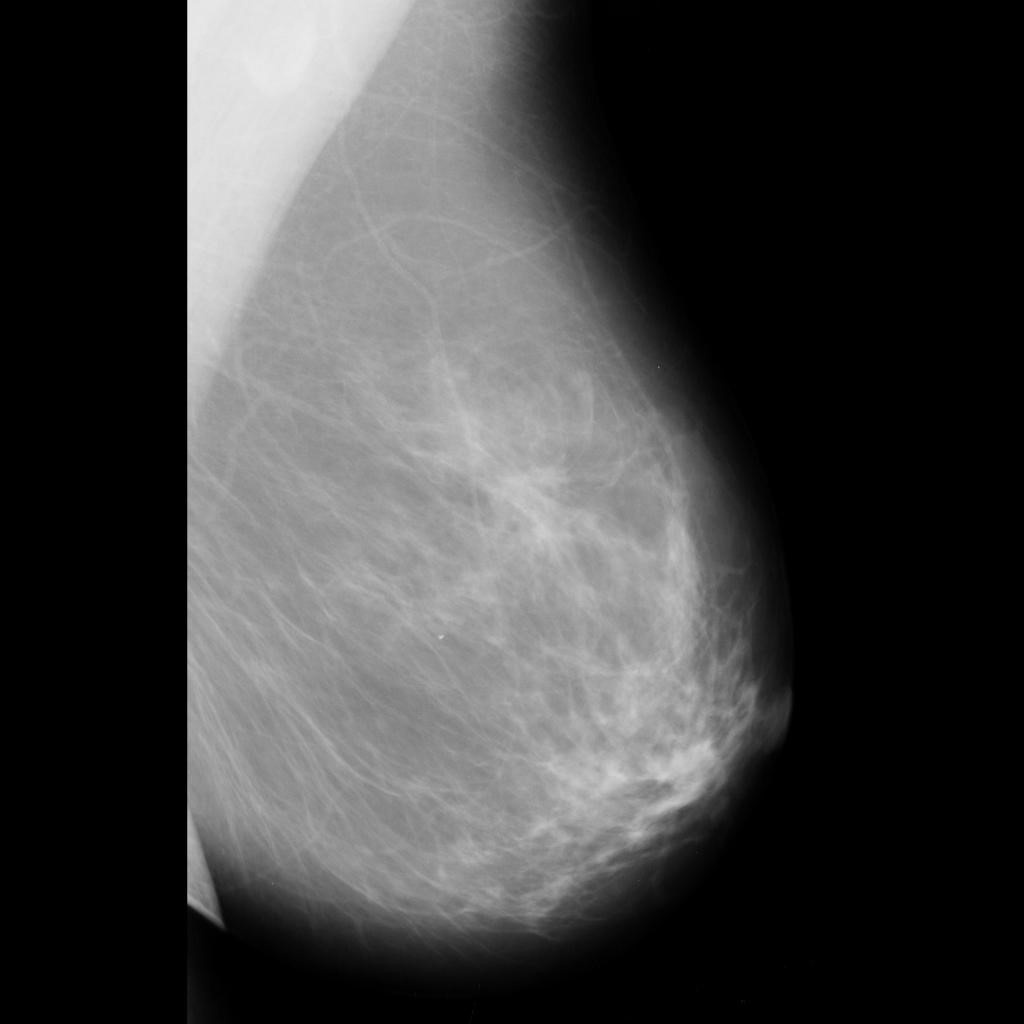

benign